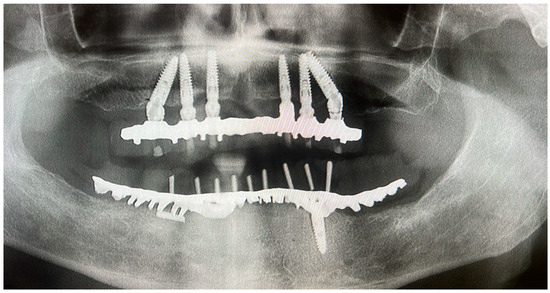

The Effectiveness and Predictability of BioHPP (Biocompatible High-Performance Polymer) Superstructures in Toronto-Branemark Implant-Prosthetic Rehabilitations: A Case Report

3. Case Presentation